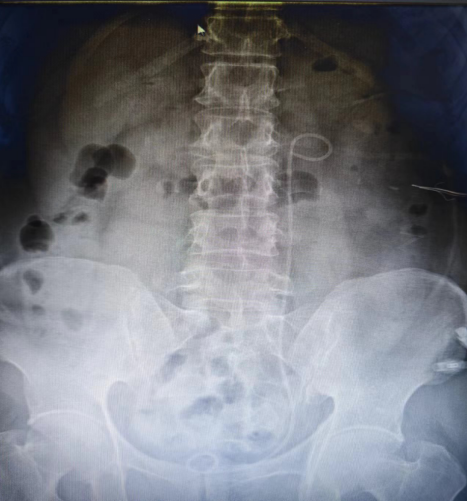

术后腹部平片

患者男性46岁,身体质量指数(BMI)27,左侧输尿管2cm结石嵌顿导致左肾重度积水,要求入我院行手术治疗。